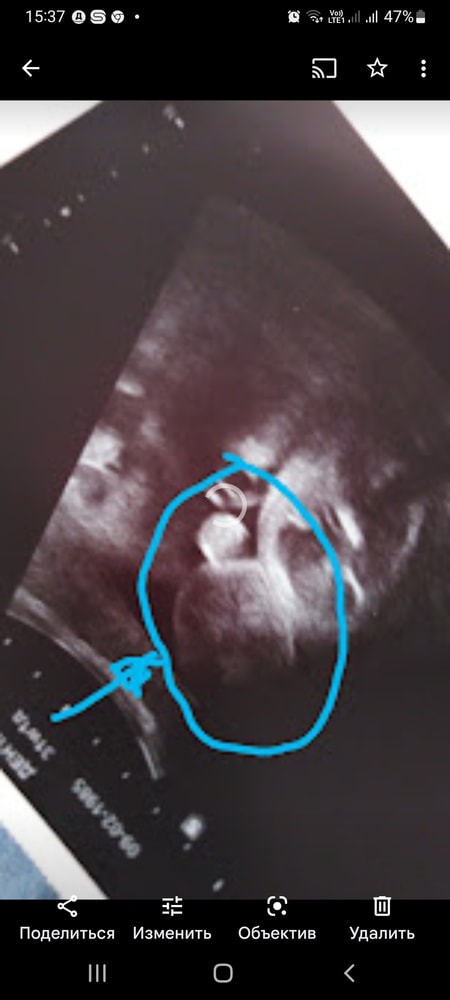

Вот так выглядел мальчик в 20 недель точнее не помню уже сколько недель было , примерно. А девочка как раз фото как у вас, так что узист сказал?

D.S, у мальчиков вот как у меня фотка. Муж просил фото узи, что там наследник, врач не поскупилась с ракурсом🤣